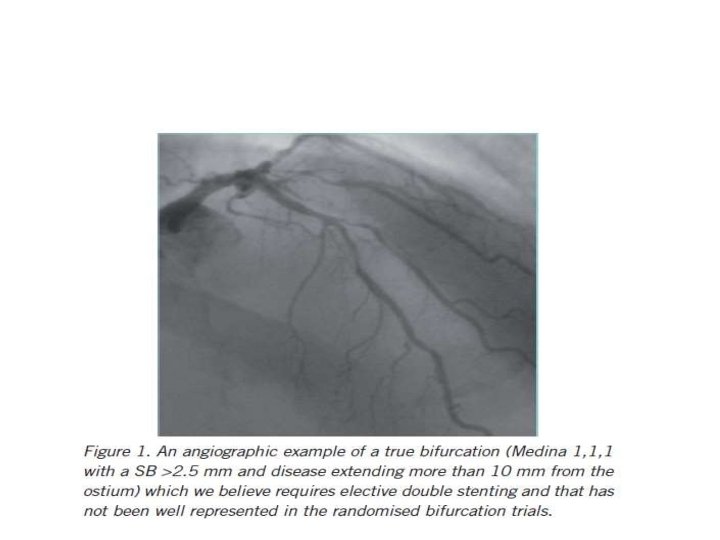

When to use elective two stents?